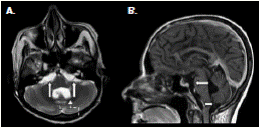

Figura 3 Resonancia magnética cerebral. A. Corte axial potenciado en T2, en el cual se observa dilatación y obstrucción del cuarto ventrículo (deformidad ventricular, flecha discontinua) y dilatación de cisternas pontocerebelosas bilaterales (flechas continuas). B. Corte sagital, potenciado en T1 con contraste, en el cual se observa dilatación de las cisternas prepontina (flecha unidireccional) y peribulbar, y obstrucción del agujero de Magendie (comprobada por cirugía) (flecha bidireccional)

Figura 4 Resonancia magnética cerebral. A. Corte coronal, potenciado en T2, en el cual se observa dilatación de la cisura coroidea posterior derecha con un diámetro mayor de 23 mm, debida a quiste de cisticercosis racemosa (sic) (flecha curva). B. Corte axial, potenciado en T1 con contraste, en el cual se observan quistes por cisticercosis racemosa (sic) en la cisura coroidea posterior derecha (flecha curva) y en valle silviano izquierdo (flecha recta)

Ante la sospecha de vómito de origen central, se practicó una resonancia magnética cerebral que evidenció múltiples dilataciones de las cisternas y obstrucción del cuarto ventrículo (figura 3) y (figura 4); el líquido cefalorraquídeo tenía aspecto claro, 13 mg/ dl de proteínas, 73 mg/dl de glucosa, no presentaba leucocitos, y se registraron 3 eritrocitos por mm3; la tinción de Gram y el cultivo para bacterias resultaron negativos. Asimismo, se hizo una exploración del cuarto ventrículo por craneotomía suboccipital, mediante la cual se detectó aracnoiditis con obstrucción del agujero de Magendie, e inflamación aguda y crónica confirmada por biopsia. Se diagnosticó, entonces, vómito incoercible de origen central, secundario a neurocisticercosis racemosa (sic) y obstrucción del cuarto ventrículo, probablemente por aracnoiditis grave.

En los dos casos que se presentan, la neurocisticercosis racemosa (sic) se acompañó de hidrocefalia y aracnoiditis; en el primer caso, además, se detectó vasculitis de la arteria cerebral media derecha en sus porciones proximales adyacentes a las cisternas de la base y la silviana derecha, relacionada con la presencia de cisticercos (figura 1). En el segundo caso, se detectó dilatación y obstrucción del cuarto ventrículo por aracnoiditis (figura 3), hallazgo que explica la causa del vómito incoercible, debido a su estrecha relación anatómica con el área postrema (control del vómito).